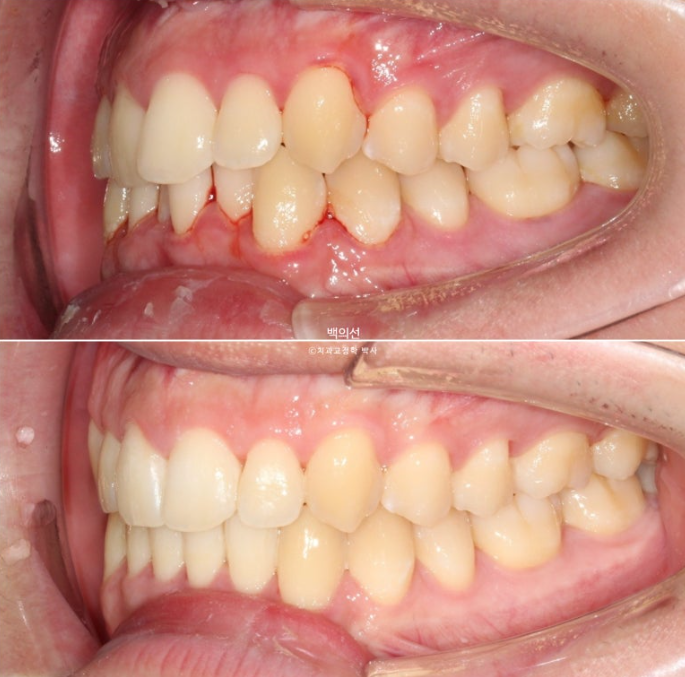

25.02~25.08